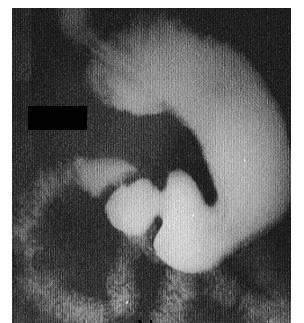

Современные технологии в медицине: рентгенодиагностика заболеваний желудка